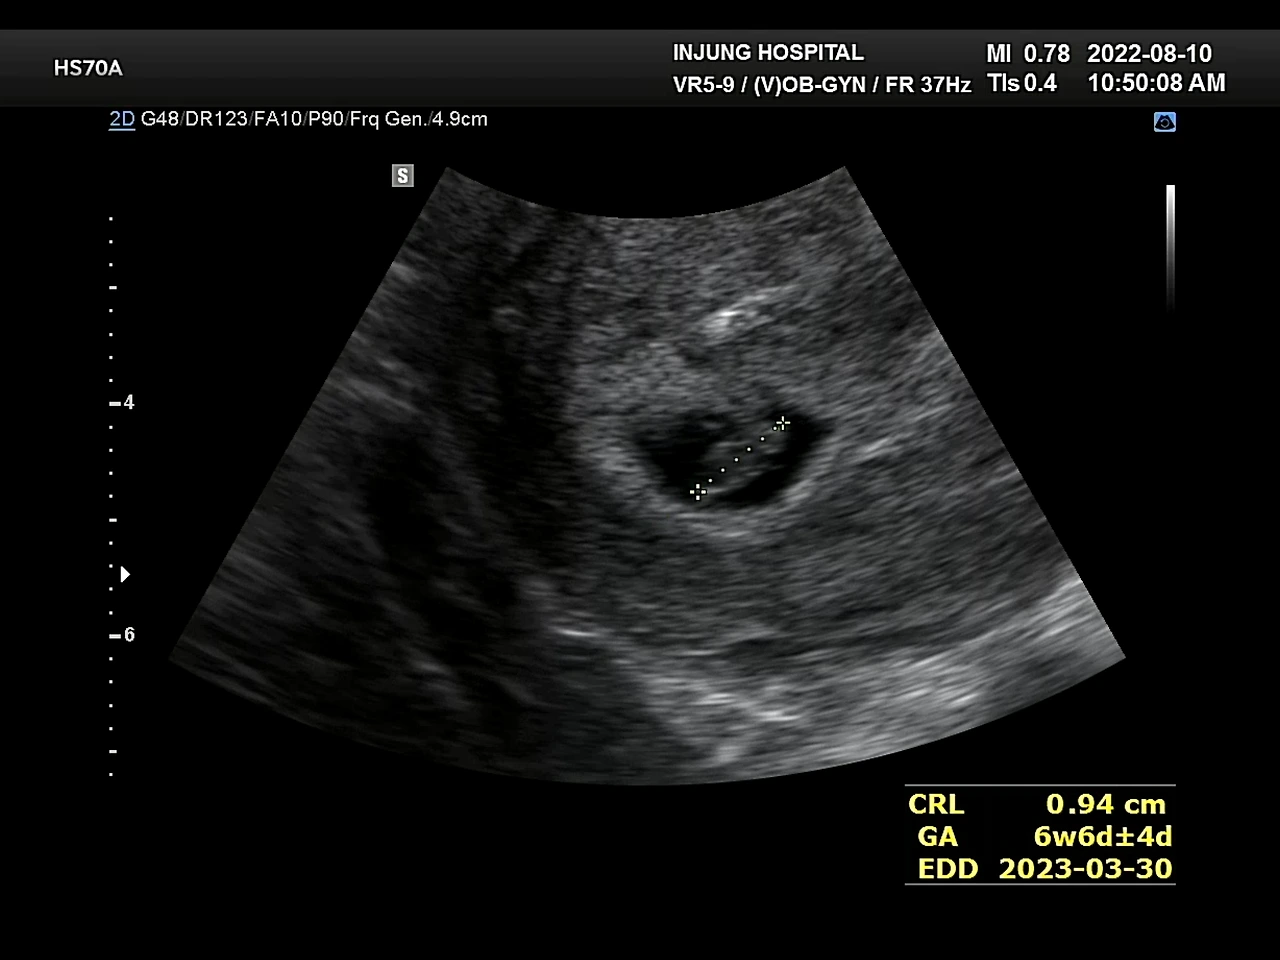

테스트기를 하고 1주일 뒤 병원을 찾았다. 아기집을 보고 젤리곰같은 태아도 봤다. 심장도 잘 뛰고 있었다. 벌써 6주 6일. 혹시나 임신이 아니면 어쩌지, 다른 문제가 생긴거면 어떡하지라는 걱정들이 무색했다.